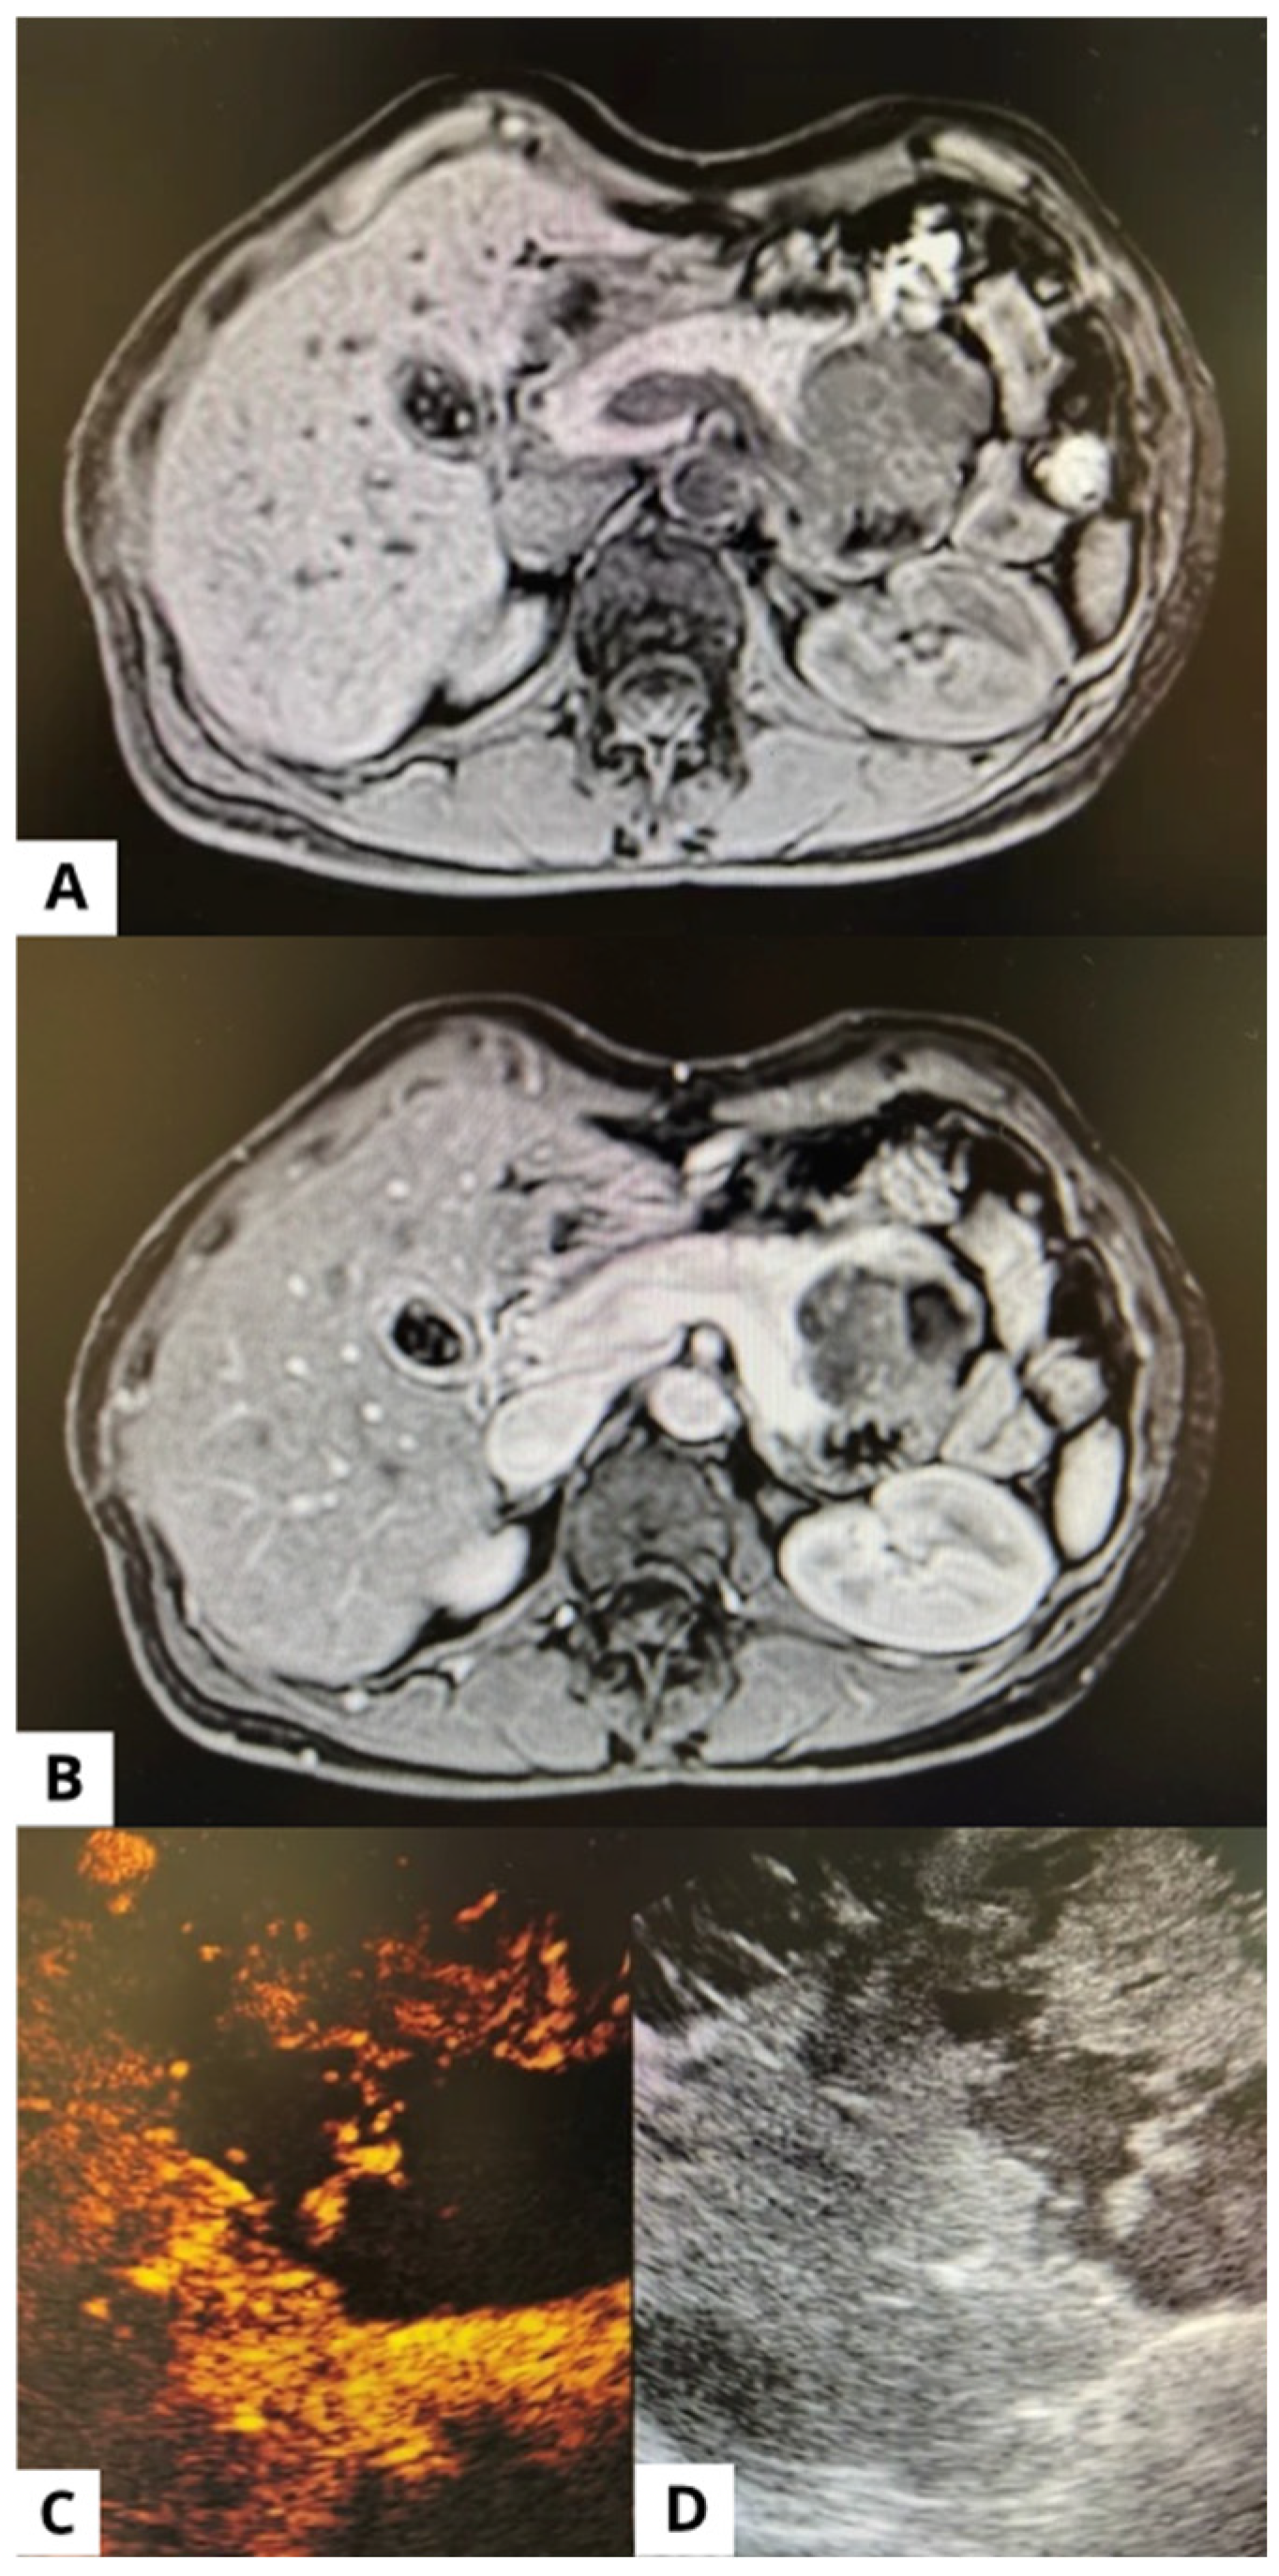

3.1. Endoscopic Ultrasound (EUS)

3.3. Radiology